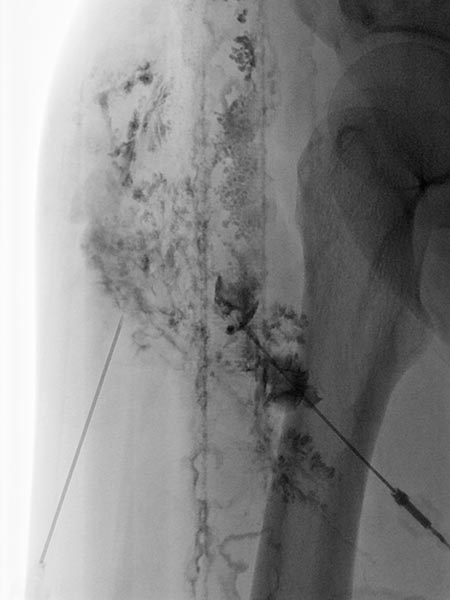

Direkte Lymphographie mit wasserlöslichem Kontrastmittel in Direktpunktionstechnik unter sonographischer Steuerung.

Es gelingt hier mehrfach die dysplastischen, erweiterten Lymphkanäle der LM im Subkutangewebe zu punktieren.

In diese wird dann das Picibanil (OK-432) als Sklerosierungsmittel injiziert um über die Entzündung die kutanen dysplastischen Lymphkanäle abzudichten.

Lymphographie in Direktpunktionstechnik unter sonographischer Steuerung.

Das subkutane Lymphgefäßsystem ist stark dysplastisch, zum Teil dilatiert und bizarr fuchsbauartig erweitert. Normale Lymphgefäße sind deutlich kleiner.

Auch hier wird Picibanil (OK-432) injiziert zur entzündungsinduzierten Lymphgefäßsklerosierung und Abdichtung der Haut.